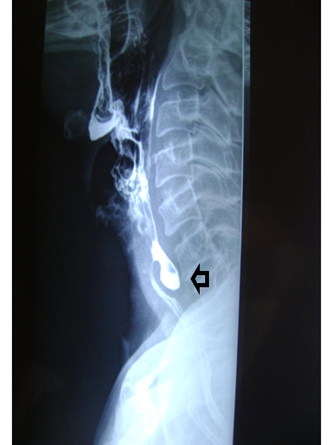

The diagnosis is made by performing a barium transit that allows to see the diverticulum, its size and topography. It is important to evaluate the three swallowing times 1) oropharyngeal 2) pharyngeal esophageal 3) esophageal. The barium clearance, elimination times, and the cricopharyngeal cleavage approximately in the 6th cervical vertebra, which is necessary to know for the interpretation of clinical pictures, will be observed (Figure 2). Upper endoscopy is not strictly necessary for the diagnosis, however it could be complementary, assessing the presence of structural changes in the mucosa as well as differential diagnoses.10 Esophageal manometry and video fluoroscopy provide data regarding pathogenesis.11

Figure 2 Barium transit. Gastric esophagus barium study. Zenker's diverticulum is observed in the posterior pharyngeal esophageal face marked with black arrow.

Male patient, 74 years old, hypertensive with no other history. He consults for dysphagia for solids, halitosis, regurgitation and noisy swallowing of approximately 3 to 4 years of evolution. He is evaluated with high endoscopy and barium transit.

The endoscopy highlights immediately above the upper esophageal sphincter, a drop in a blind pouch, which appears to be a wide cervical esophageal diverticulum. Mucosa without alterations. Given the endoscopic findings, it was decided to request an esophageal transit. From the pharyngeal esophageal transit, a 53mm posterior diverticulum compatible with Zenker's diverticulum is highlighted. It fills quickly and is very slow to evacuate. The rest of the esophageal and pharyngeal esophageal passage of usual caliber without evidence of other alterations. It was discussed in the athenaeum and surgery was decided because it was a diverticulum larger than 50 mm. Diverticulectomy and myotomy of the cricopharyngeal muscle. During hospitalization, the patient reported controlled pain, without dysphagia, barium esophageal transit was performed without leakage or esophageal narrowing. Patient was discharged after 7 days tolerating oral route with wounds in good condition and without dysphagia. In postoperative controls 2-3 months after surgery, patient is tolerating oral route (liquid and solids) without difficulties, denies dysphagia, halitosis and regurgitation. Pathological anatomy of the diverticulum microscopy: esophageal mucosa with erosion, acanthosis, spongiosis and intraepithelial lymphocytic and polymorphonuclear infiltrate. Submucosa: edematous with congestive vessels and diffuse lymphoplasmacytic infiltrate. No evidence of malignancy.